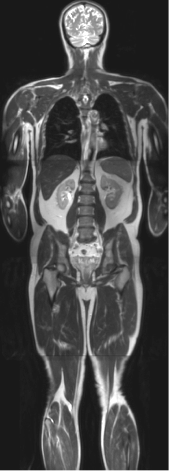

- Magnetic Resonance Imaging

The Magnetic Resonance (MR) Research program in the Department of Radiology carries out fundamental research that leads to the development of new techniques, optimization of current techniques, and improved understanding of the pathophysiology of disease. Various aspects of the research include developing techniques for rapid imaging and evaluating novel methods to extract biologically and clinically relevant physiological information. Such advances in noninvasive imaging techniques allow not only appropriate diagnosis but also improved characterization of disease following therapeutic interventions without ionizing radiation exposure. An important goal of this program is to translate these technical advances rapidly into clinical practice for improved patient care.